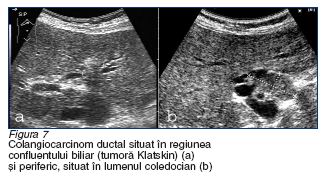

Aspecte ecografice particulare intalnite in metastazarea hepatica

a. metastazele neoplasmului

colorectal sunt multiple (poate

exista si varianta unica!), relativ voluminoase (in circa 3/4

din cazuri au dimensiuni cuprinse intre 3 si 10 cm). Delimitarea tumorala prin halou

este intalnita

in circa 1/2 dintre cazuri,

iar cea neta,

doar in 1/5 dintre cazuri. Structura metastazelor recto-colice este in general neomogena, fara particularitati semnificative ale

ecourilor returnate. Exista o tendinta a metastazelor inalt diferentiate de a ajunge la dimensiuni mari

si de a dezvolta calcificari centrale, intratumorale (figura 8).